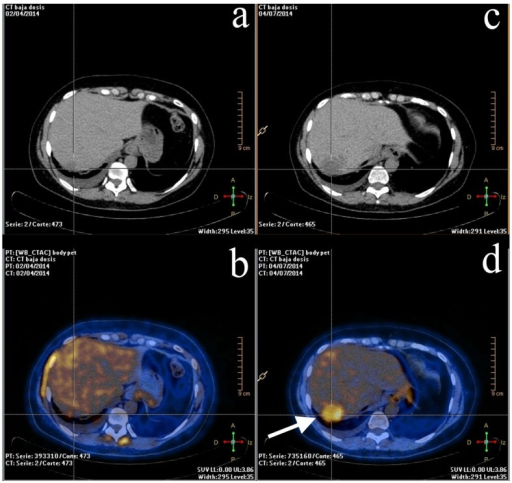

3a To D A 35 Year Old Female With Known Breast Cancer Underwent Pet Ct Download Scientific Diagram

www.researchgate.net